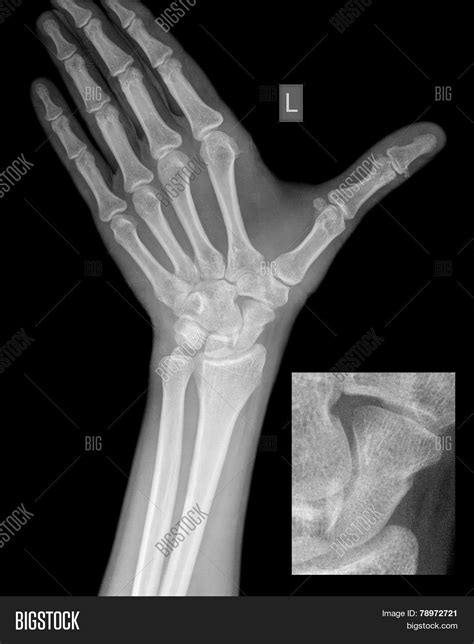

Hand fractures can occur in various bones and in different ways. Some of the most common types include:

• Metacarpal Fractures: These occur in the long bones of the hand, known as metacarpals. They are often caused by direct trauma, such as a punch or a fall.

• Phalangeal Fractures: These affect the bones of the fingers and thumb. They can be caused by crushing injuries, jamming, or twisting.

• Scaphoid Fractures: These occur in the scaphoid bone, one of the small bones in the wrist. They are often caused by a fall onto an outstretched hand.

• Distal Radius Fractures: These affect the end of the radius bone in the forearm, near the wrist. They are common in falls and can be quite painful.

Each type of fracture may require a different approach to treatment, so accurate diagnosis through a broken hand x-ray is crucial.